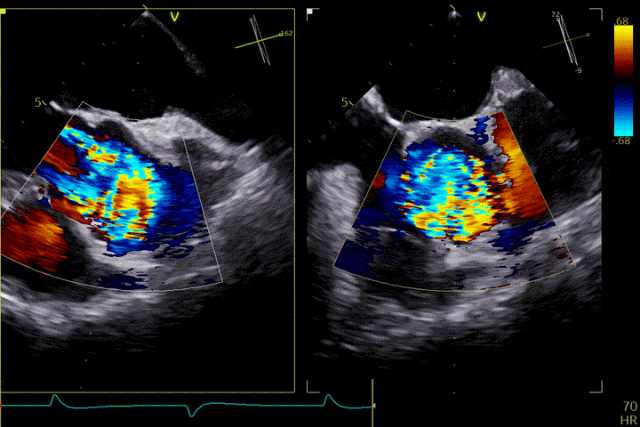

术前超声

术后效果

患者主动脉瓣重度反流纠正,术后无反流、无瓣周漏。术后心脏彩超显示人工生物瓣启闭良好,平均跨瓣压差2mmHg,流速正常。患者恢复情况良好,心功能较术前有了明显改善。